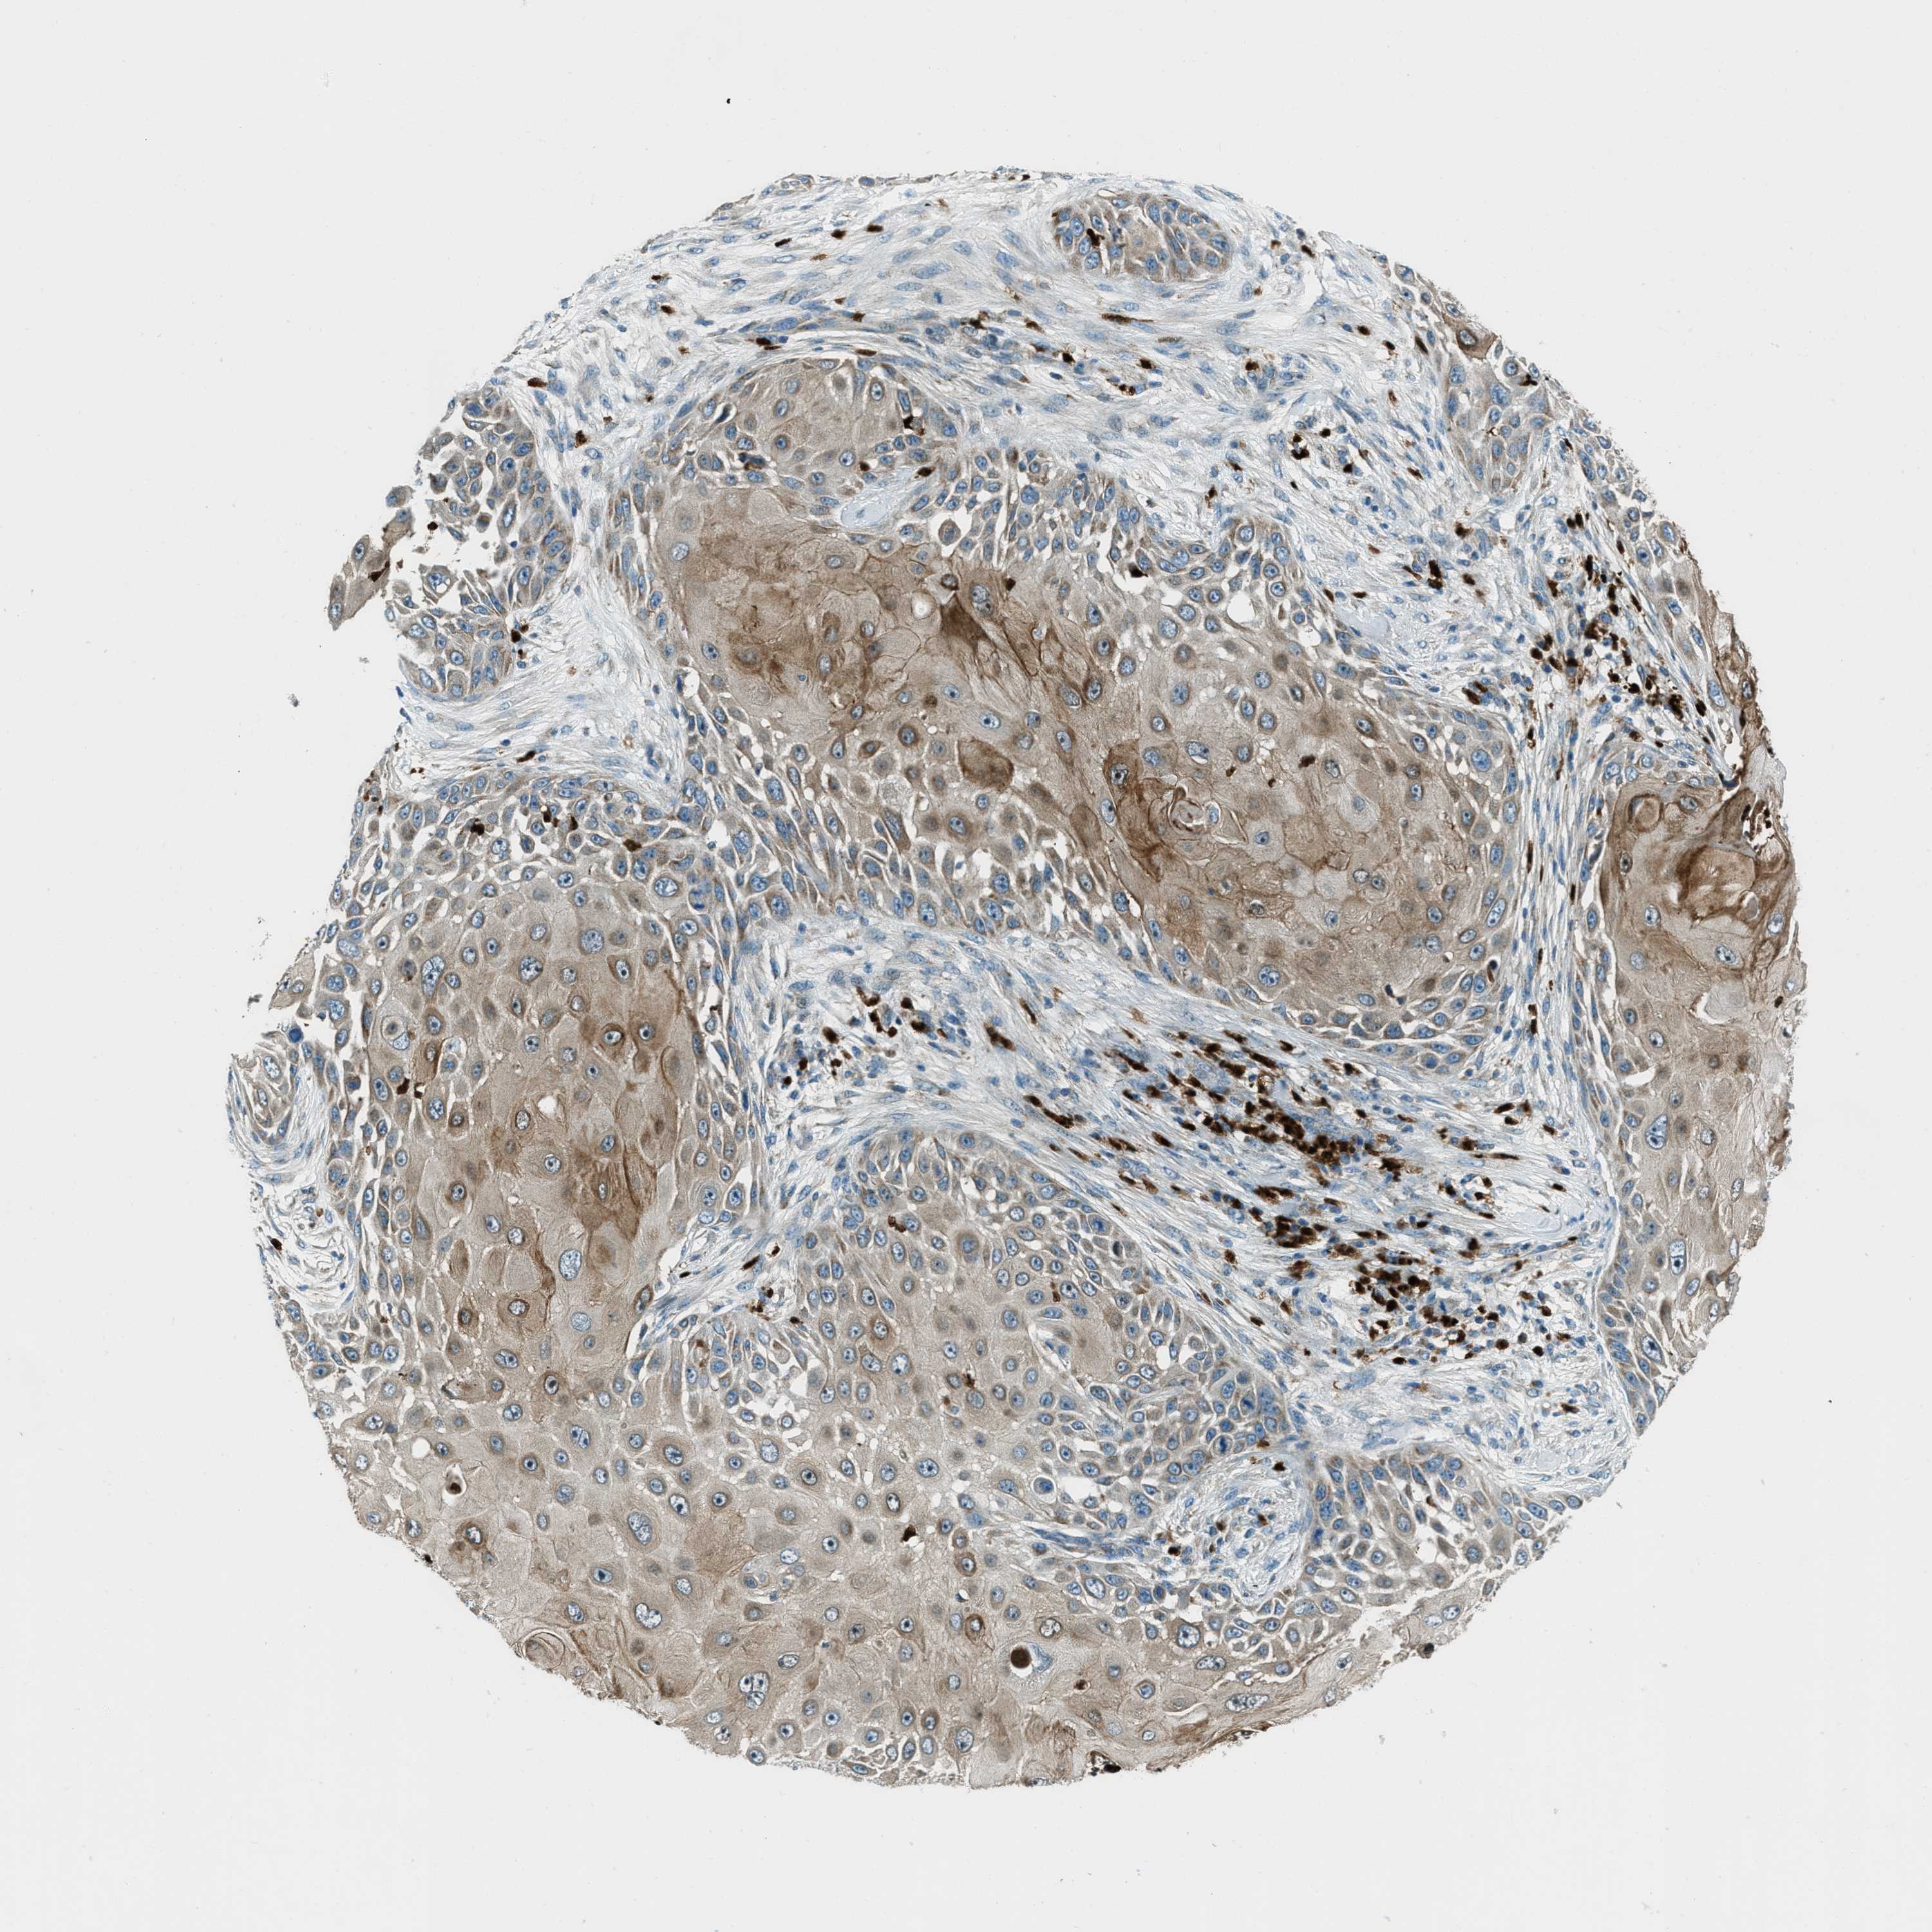

SKIN CANCER - Protein expressioni

A mouse-over function shows sample information and annotation data. Click on an image to view it in a full screen mode. Samples can be filtered based on level of antibody staining by selecting one or several of the following categories: high, medium, low and not detected. The assay and annotation is described here.

Each image is clickable and will lead to virtual microscopy that enables deeper exploration of all samples and also displays staining intensity scores, fraction scores and subcellular localization as well as patient and tissue information for each sample.

Antibody HPA017322

Staining

High

Intensity

Strong

Quantity

>75%

Location

Nuclear

Squamous cell carcinoma in situ, NOS

Squamous cell carcinoma, NOS

Squamous cell carcinoma, metastatic, NOS

Basal cell carcinoma